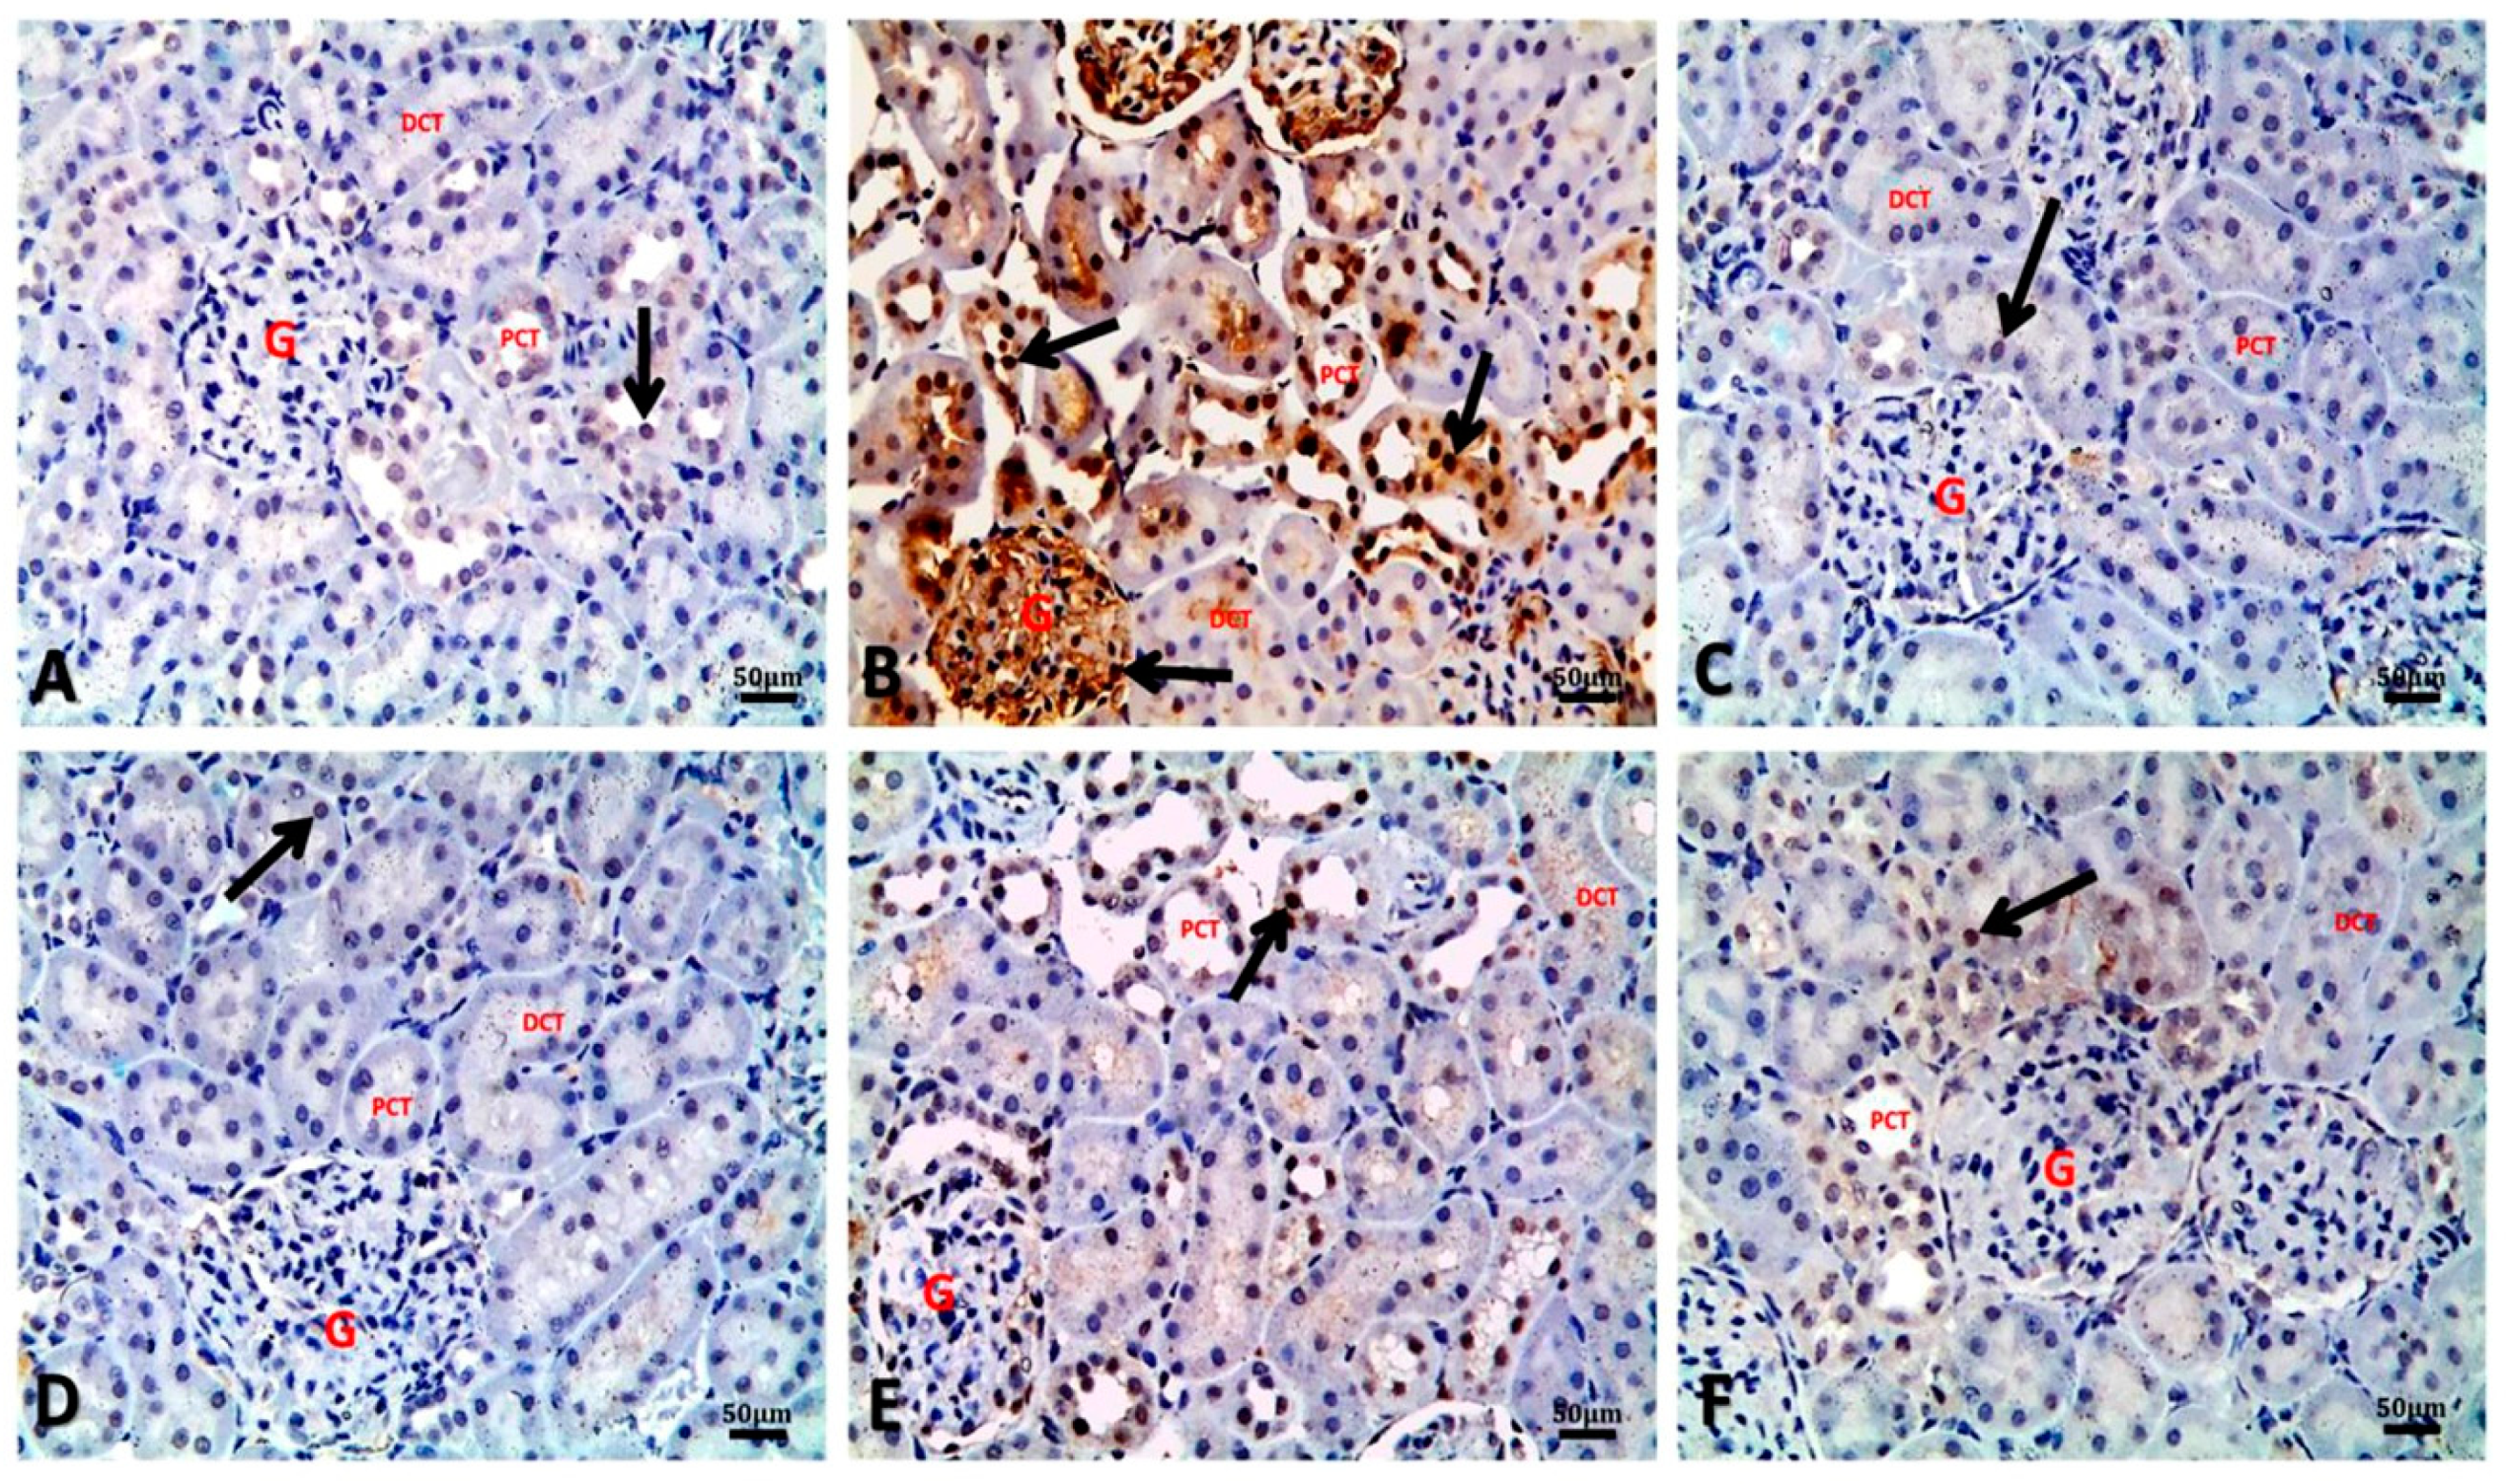

3.7. Argan Oil Modulated Betamethasone-Induced Increase of Bax and Caspase-3 and Decrease of Bcl-2 and PCNA Expressions in Renal Tissues of Rats

| IHC | Experimental Groups | |||||

|---|---|---|---|---|---|---|

| Control | BM | AO/0.5 | AO/1 | BM + AO/0.5 | BM + AO/1 | |

| Bax (% of positive cells/HPF) | 9.85 ± 0.61 c | 28.24 ± 1.43 a | 8.37 ± 0.54 c | 7.25 ± 0.31 c | 15.94 ± 1.01 b | 14.21 ± 1.05 b |

| Bcl-2 (% of positive cells/HPF) | 27.33 ± 0.88 a | 5.36 ± 0.17 b | 24.35 ± 0.54 a | 25.40 ± 0.44 a | 28.67 ± 0.50 a | 28.82 ± 0.13 a |

| Bax/Bcl-2 Ratio (% of positive cells/HPF) | 0.36 ± 0.06 b | 5.27 ± 0.73 a | 0.34 ± 0.02 b | 0.29 ± 0.03 b | 0.56 ± 0.03 b | 0.49 ± 0.02 b |

| Caspase-3 (% of positive cells/HPF) | 7.07 ± 0.72 c | 39.87 ± 2.00 a | 6.42 ± 0.36 c | 5.49 ± 0.64 c | 18.48 ± 1.73 b | 15.75 ± 1.92 b |

| PCNA (% of positive cells/HPF) | 32.75 ± 0.39 a | 10.67 ± 0.36 b | 33.35 ± 0.49 a | 34.13 ± 0.46 a | 30.48 ± 0.43 a | 31.70 ± 0.31 a |